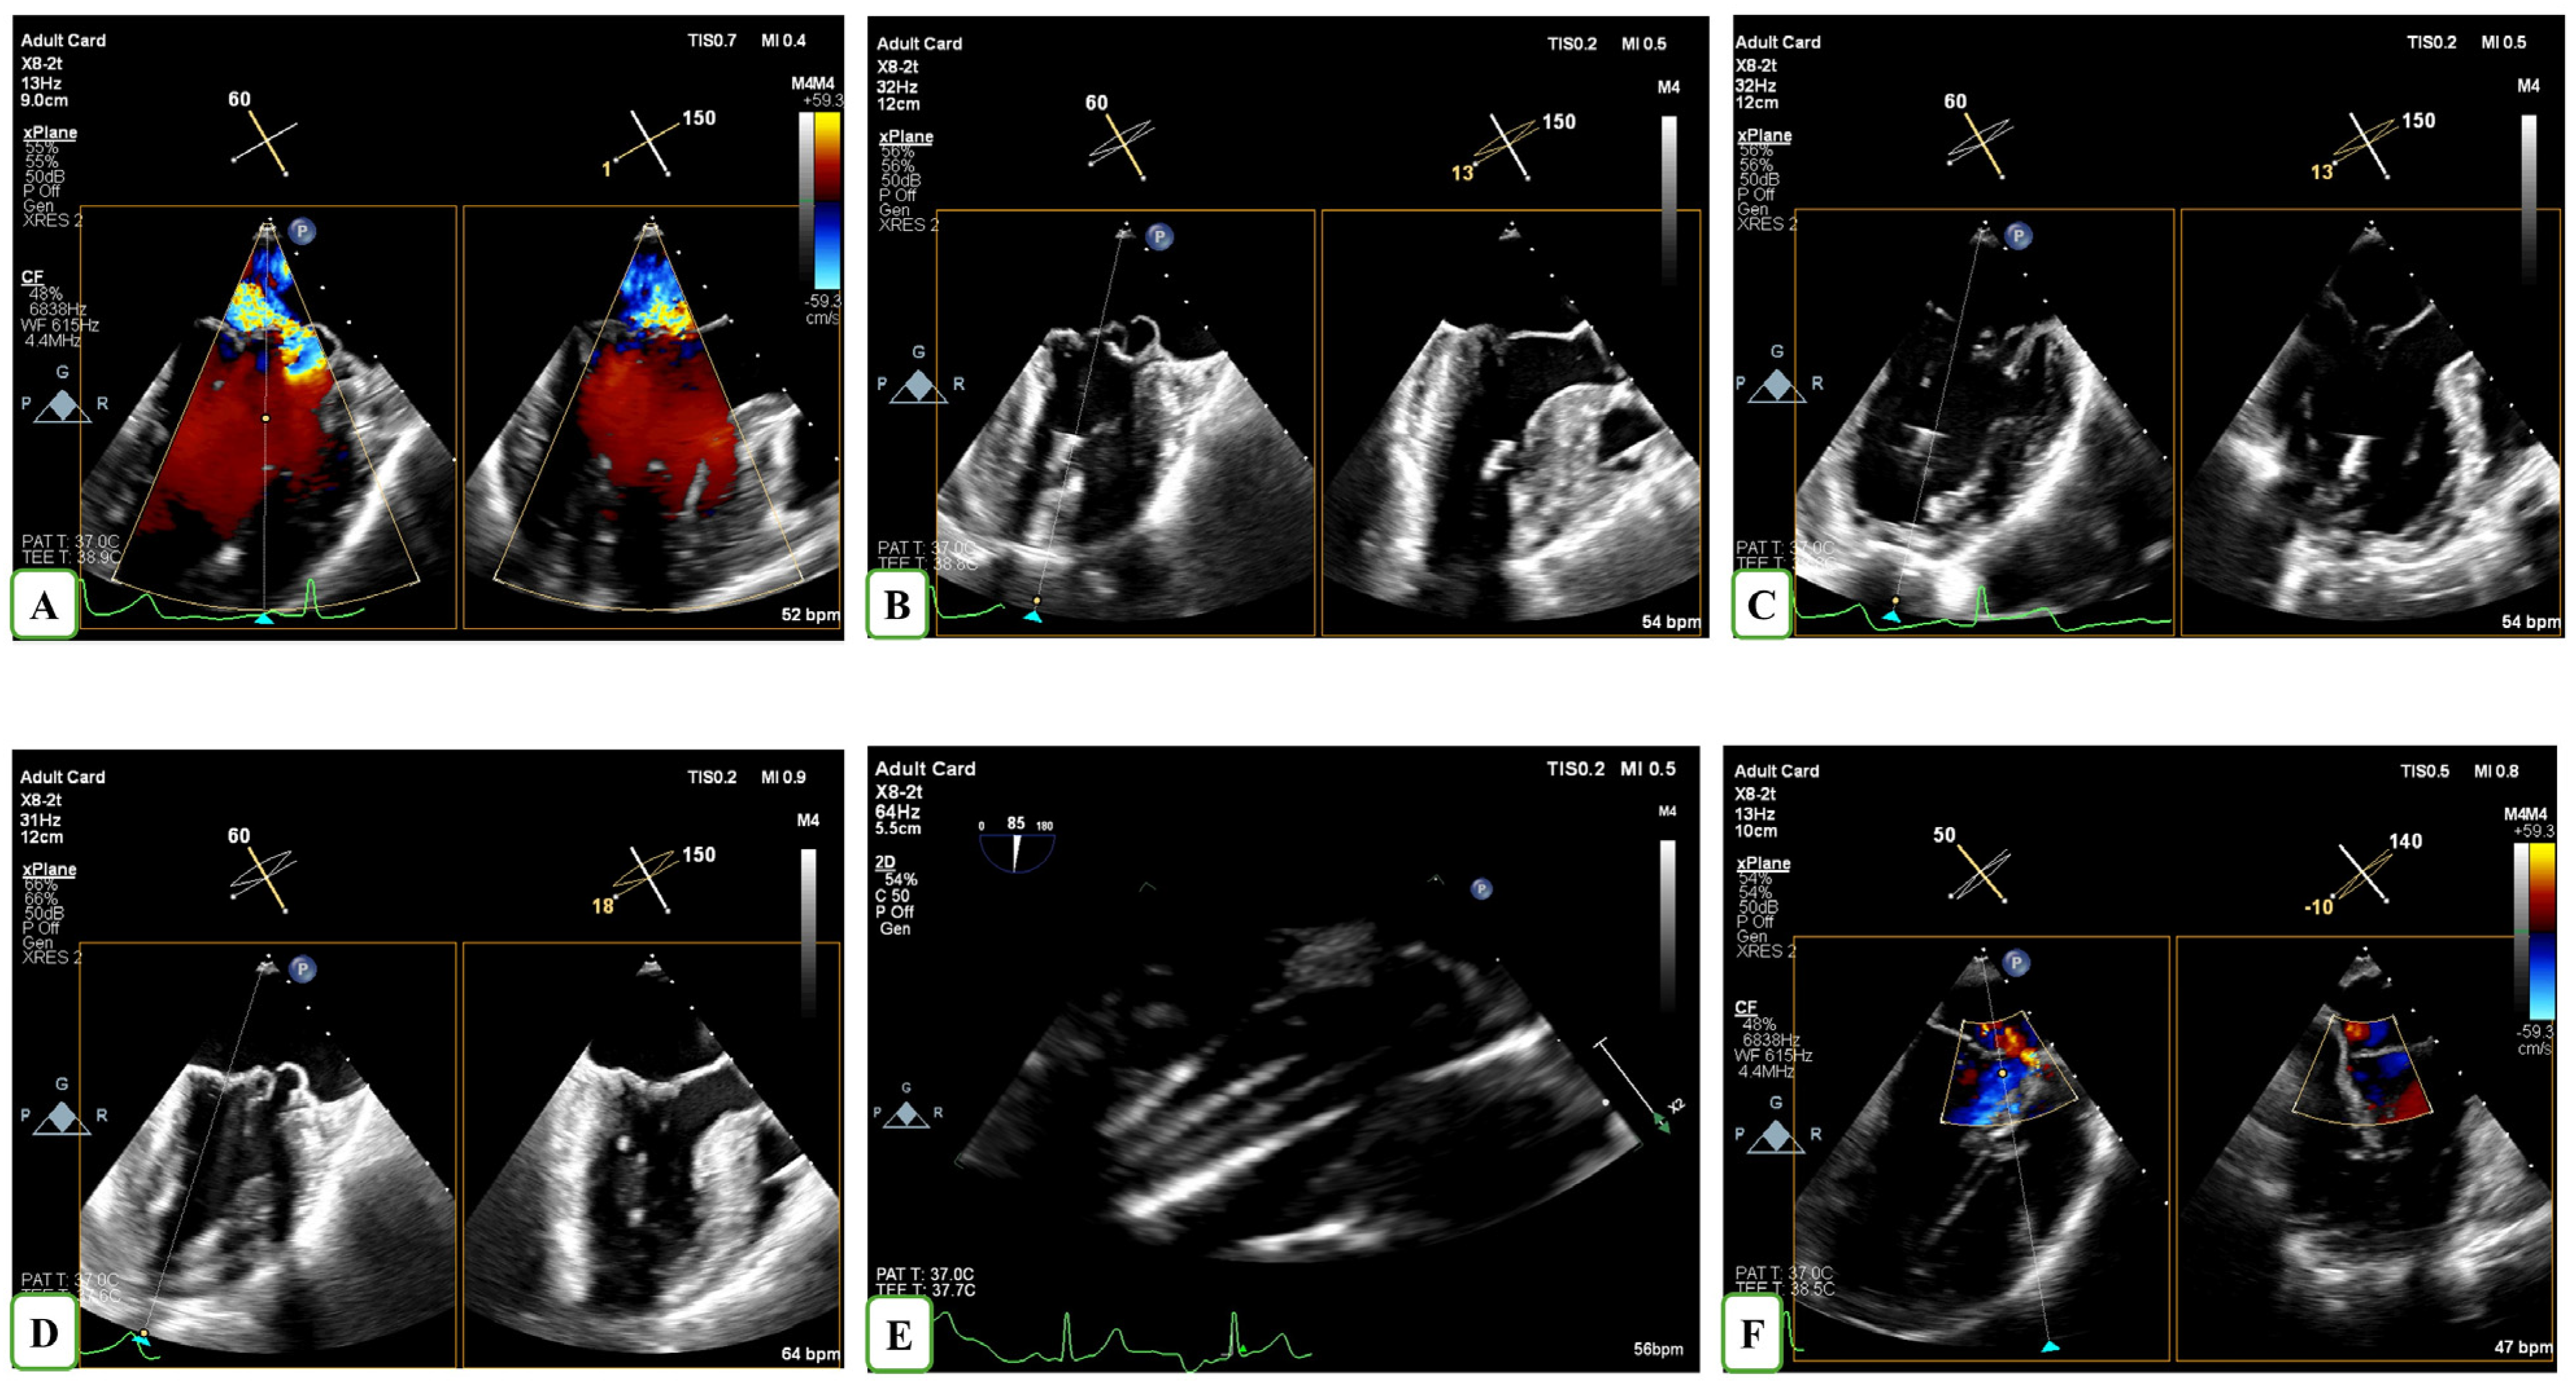

The technical part of the procedure has been described in our previous publication [13]. MV repair was conducted under general anaesthesia via a left minithoracotomy approach, lateral to the apex. The NeoChord device was introduced into the left ventricle (LV) using 3D TEE guidance and the precise leaflet capture as well as the optimization of chordal length was performed appropriately (Figure 1). Procedural success was defined as the implantation of at least two neochordae and the reduction of MR to trivial-mild and mild to moderate at the end of the procedure.

Figure 1.

TEE-guided insertion of the NeoChord device through the left ventricular apex in a patient with severe MR (A). The TEE-guided procedure is illustrated in panels (B–D) using X-Plane modality to acquire the bicommisural and 3-chamber views. Four neochordae were implanted on the posterior leaflet, as visualized using the transgastric echocardiographic view (E). Color Doppler revealed residual trivial mitral regurgitation following NeoChord implantation (F).